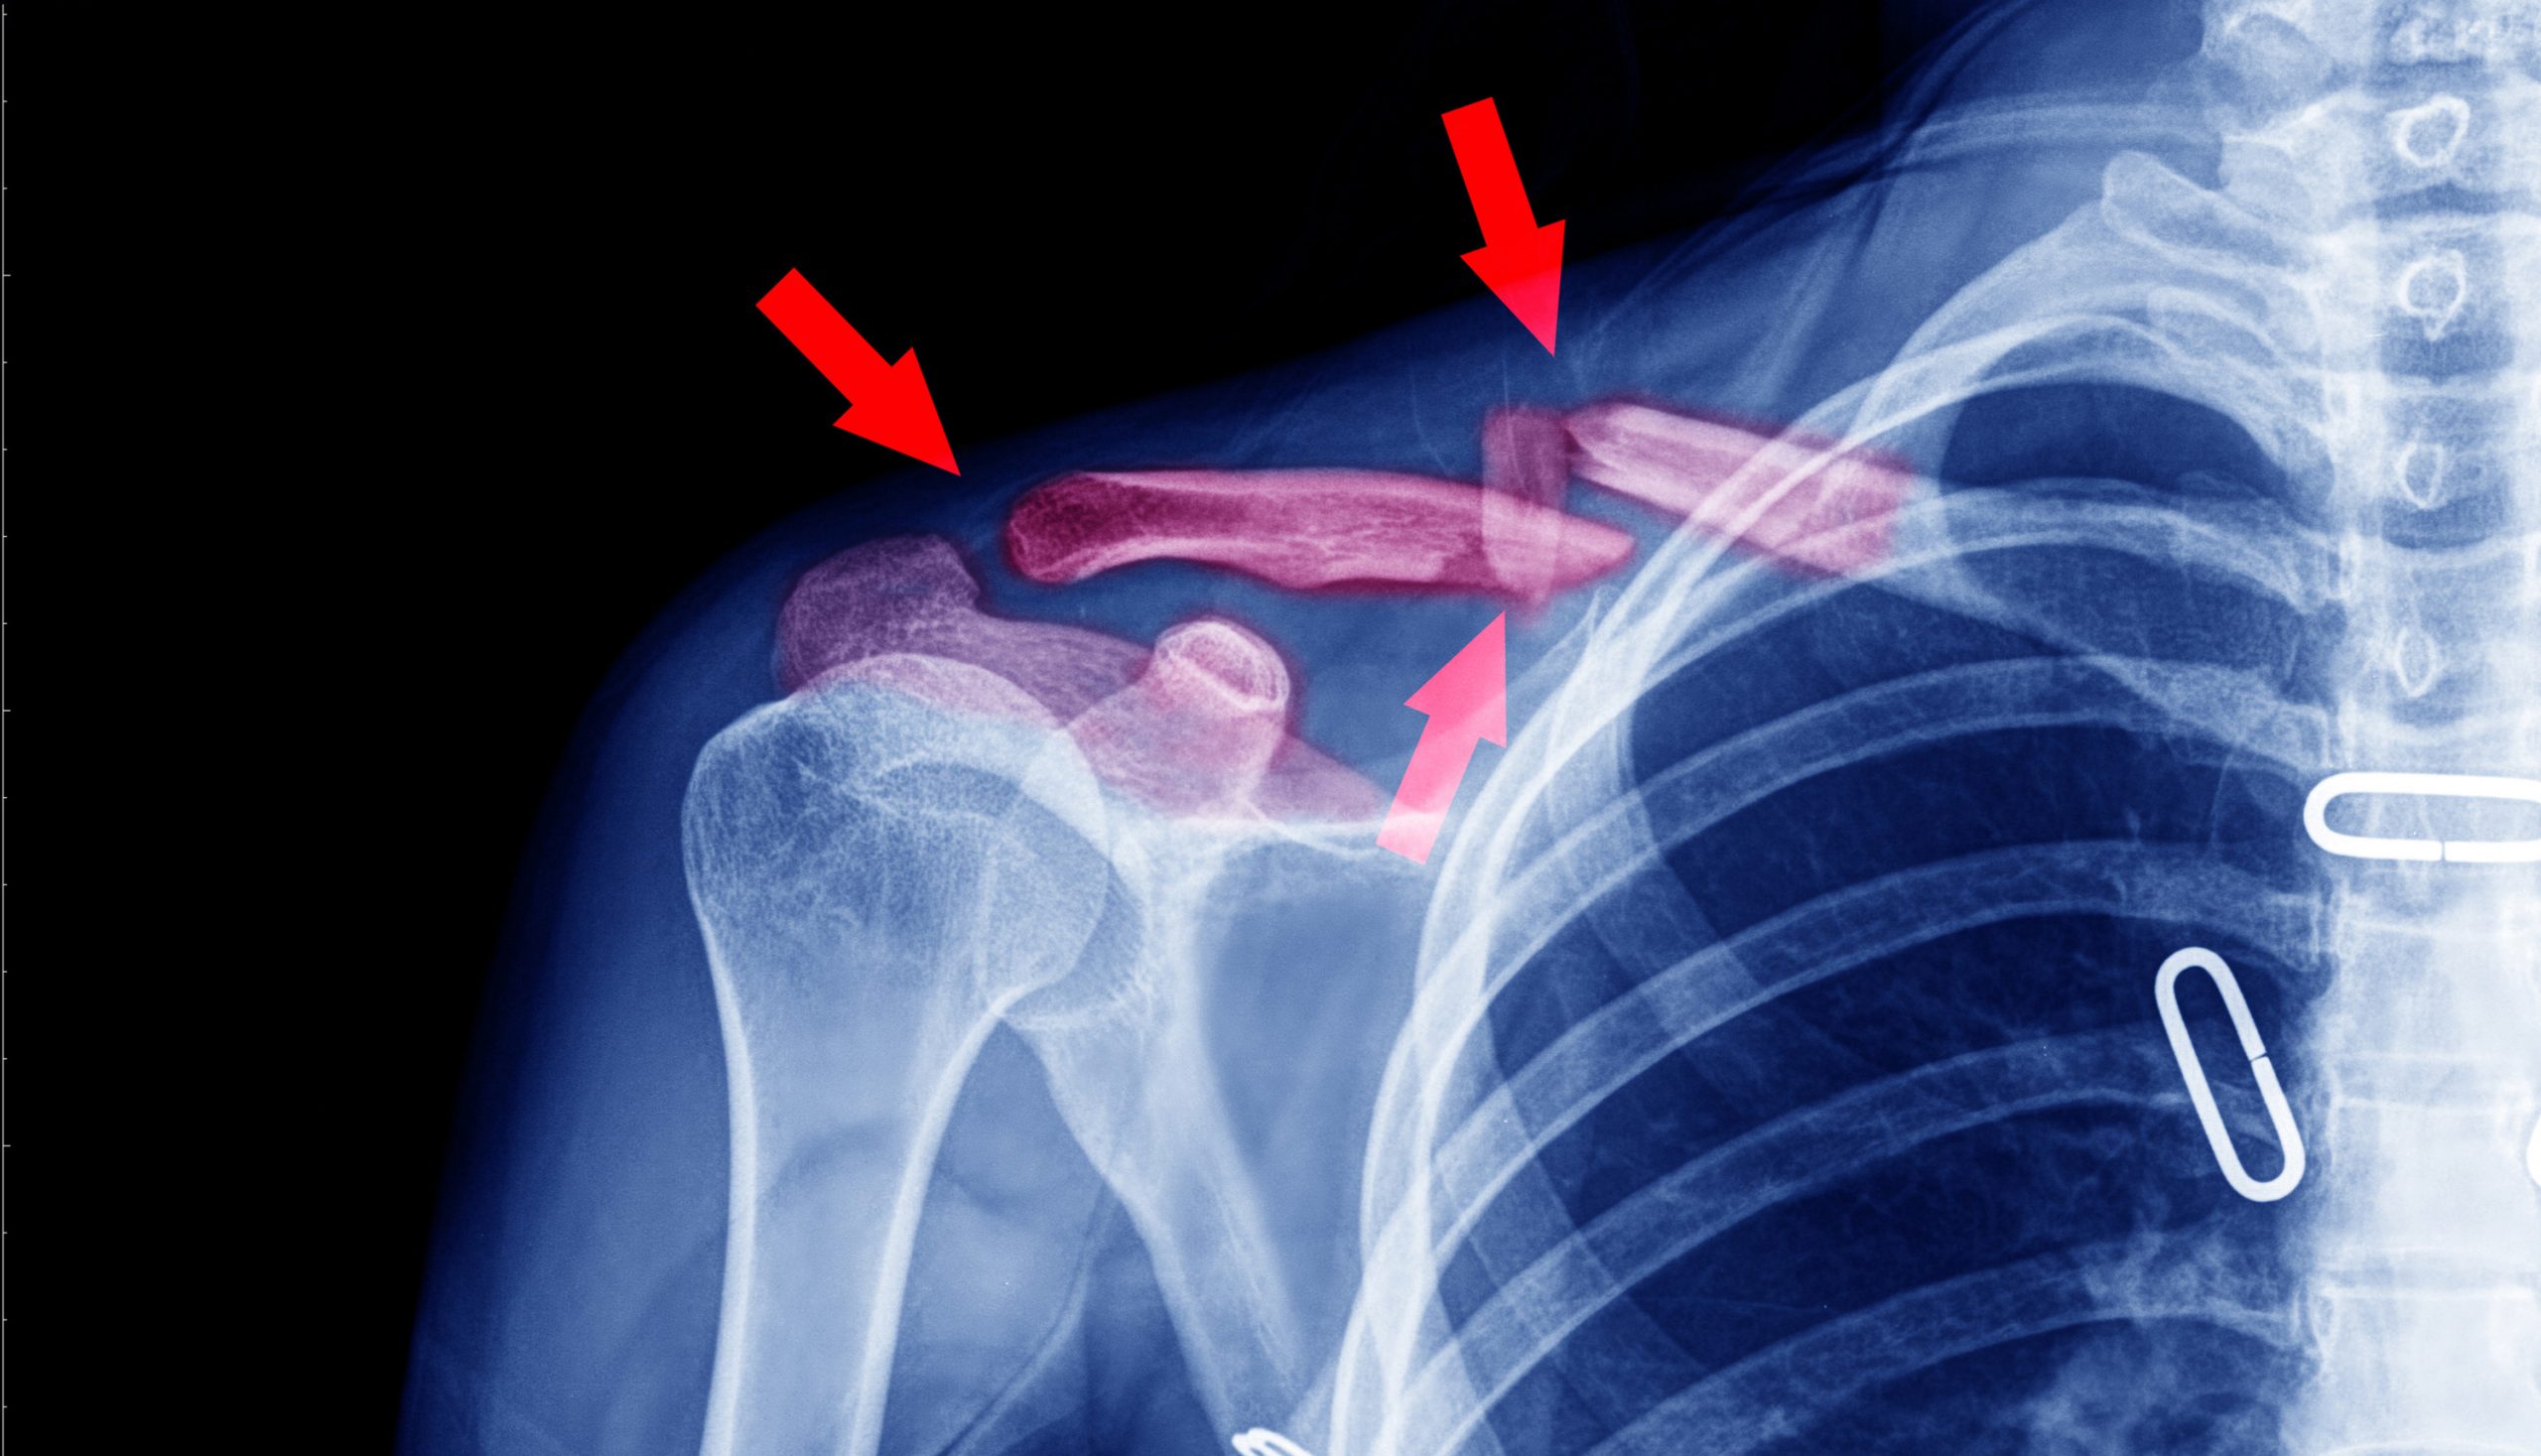

An X-ray is one of the oldest, yet still most effective, solutions for quickly diagnosing causes of pain or inflammation. Your doctor may request an X-ray if they suspect you have:

- Broken bones

X-rays send beams of radiation energy through your body. Each type of tissue absorbs this energy in varying amounts. Dense bones, for instance, absorb higher amounts of energy and show up as white on the X-ray image.

Less-dense areas, such as connective tissues, don’t absorb as much energy and appear as various shades of gray or black. Occasionally, a contrast medium is injected to help enhance the X-ray image. This is usually done through a simple intravenous (IV) injection.